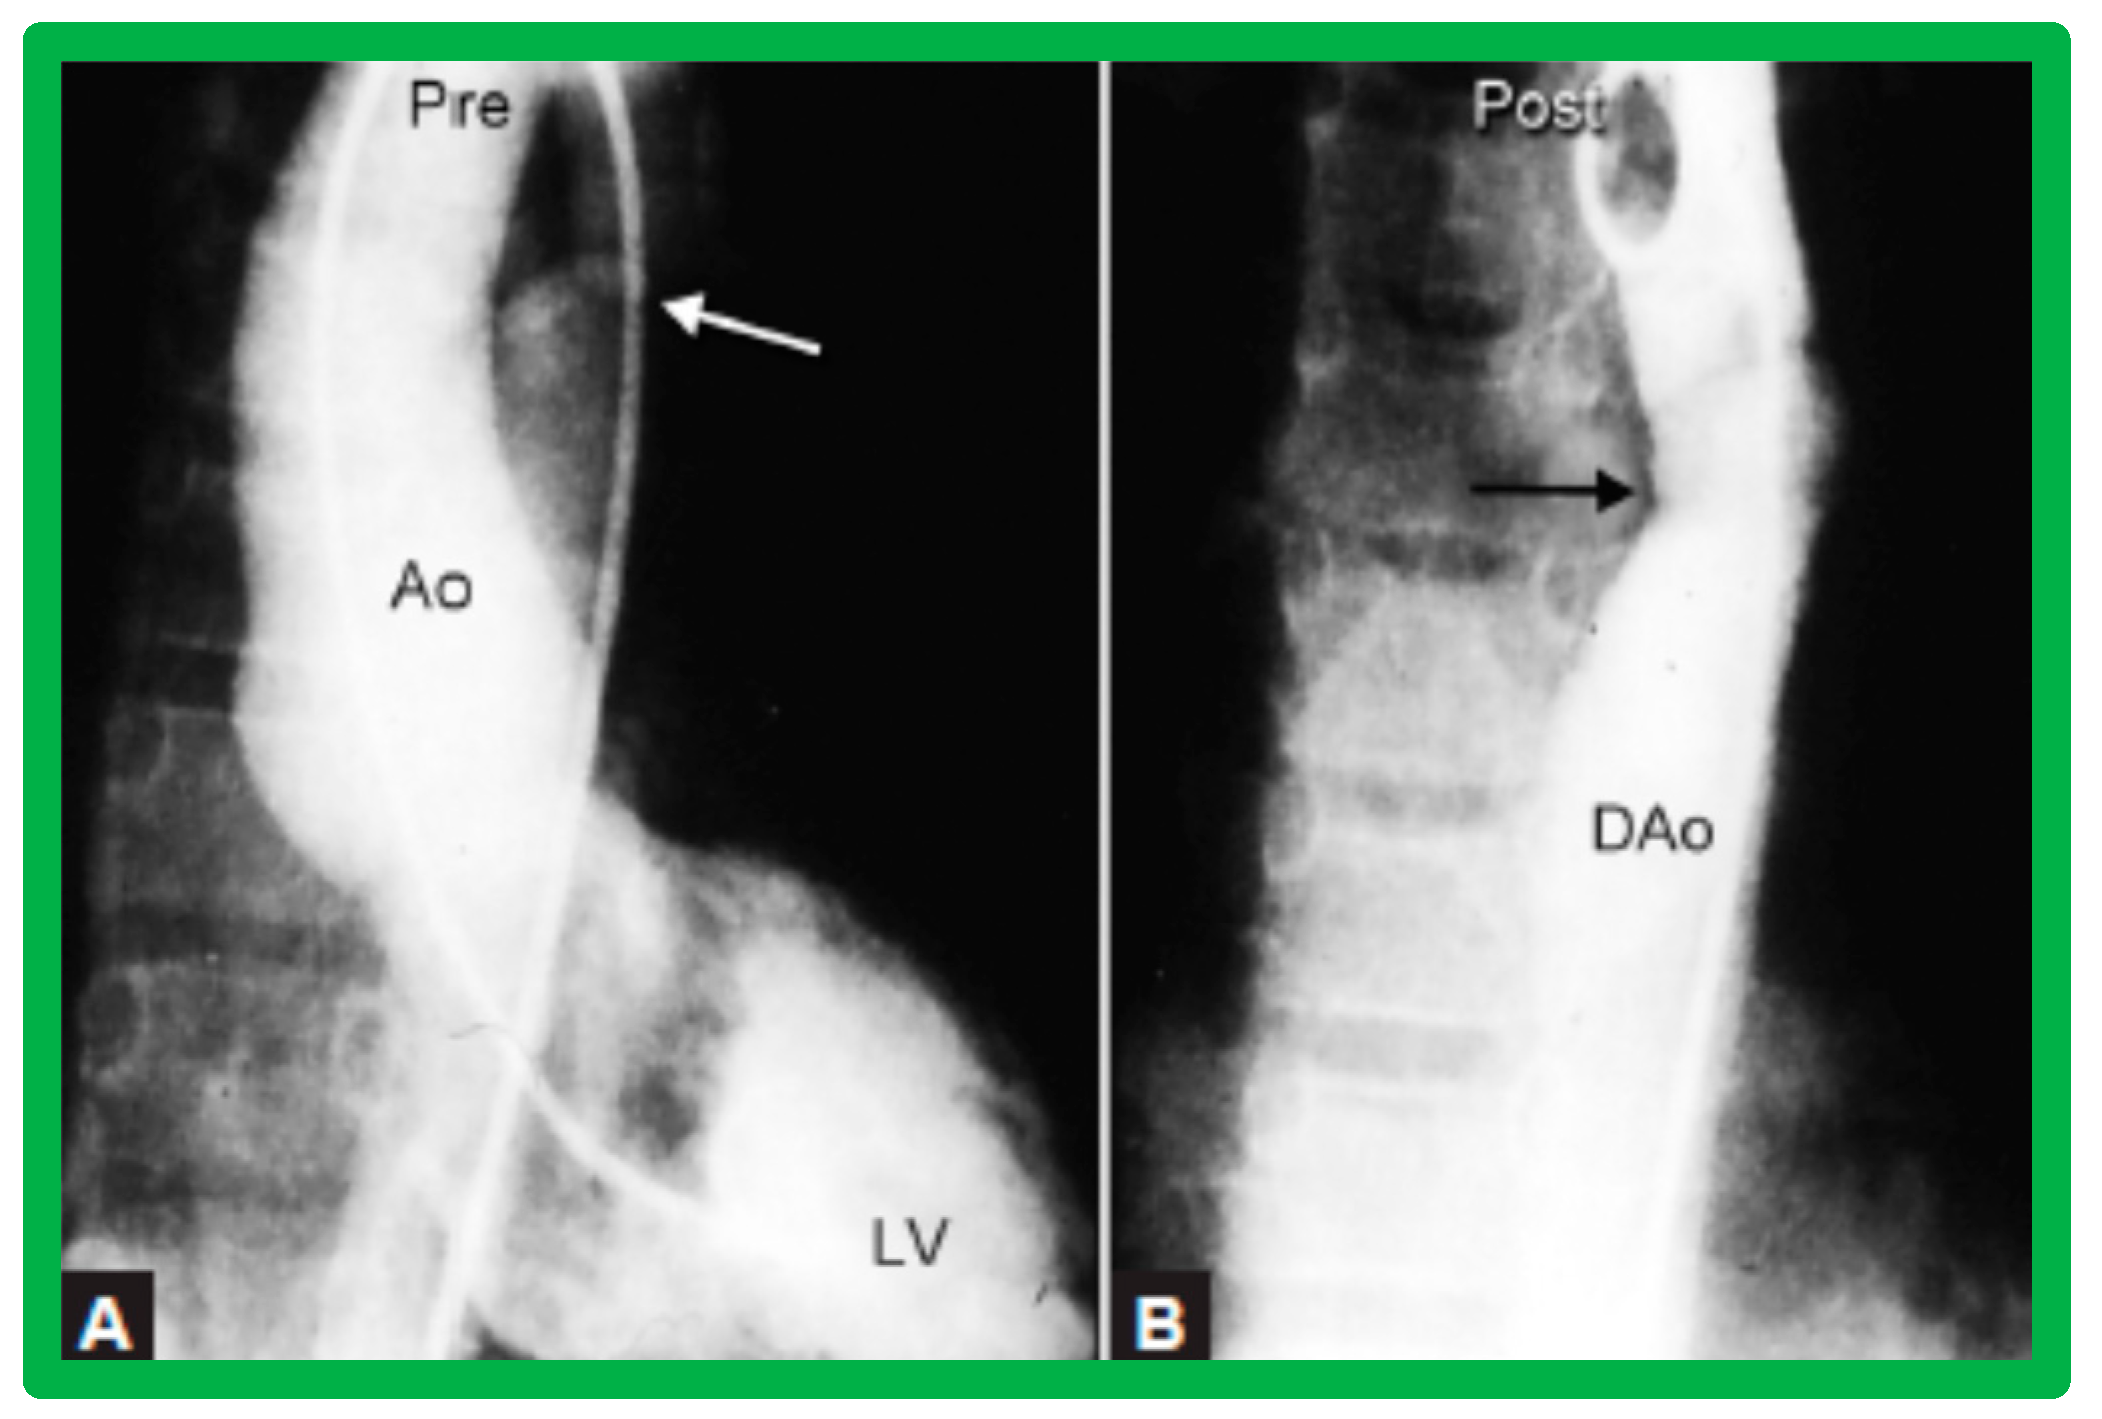

3.4. Aortic Coarctation, Postsurgical

4.4. Aortic Coarctation, Postsurgical